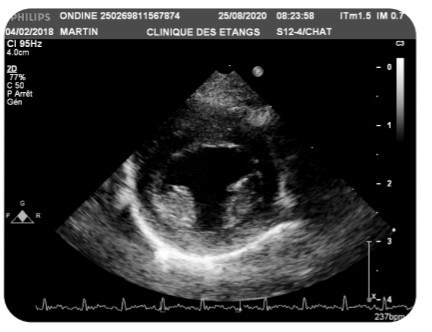

Cette dernière peut être détectée par un dépistage génétique mais également lors d’une auscultation cardiaque ou d’une échographie.

Toutefois certains chats homozygotes sains (non porteur du gène muté) pourront développer une autre forme de HCM que celle liée au gène MyBPC3 . Il est donc recommandé de réaliser des échographies cardiaques qui recherchent la présence de signes cliniques.